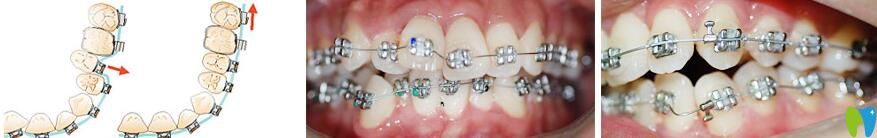

lh魔法絲矯正是自鎖嗎?

LH魔法絲線是一根神奇的超柔的線,類似于平時(shí)正畸過(guò)程中使用的傳統(tǒng)的矯正弓絲,所以可以搭配普通的金屬托槽,也可以搭配自鎖托槽,或者是冰晶托槽,冰晶自鎖托槽等等,不過(guò)相較于搭配金屬托槽,冰晶托槽更美觀一些。

lh魔法絲矯正是自鎖嗎

所以自鎖只是lh魔法絲矯正可以使用的一種方式而已。